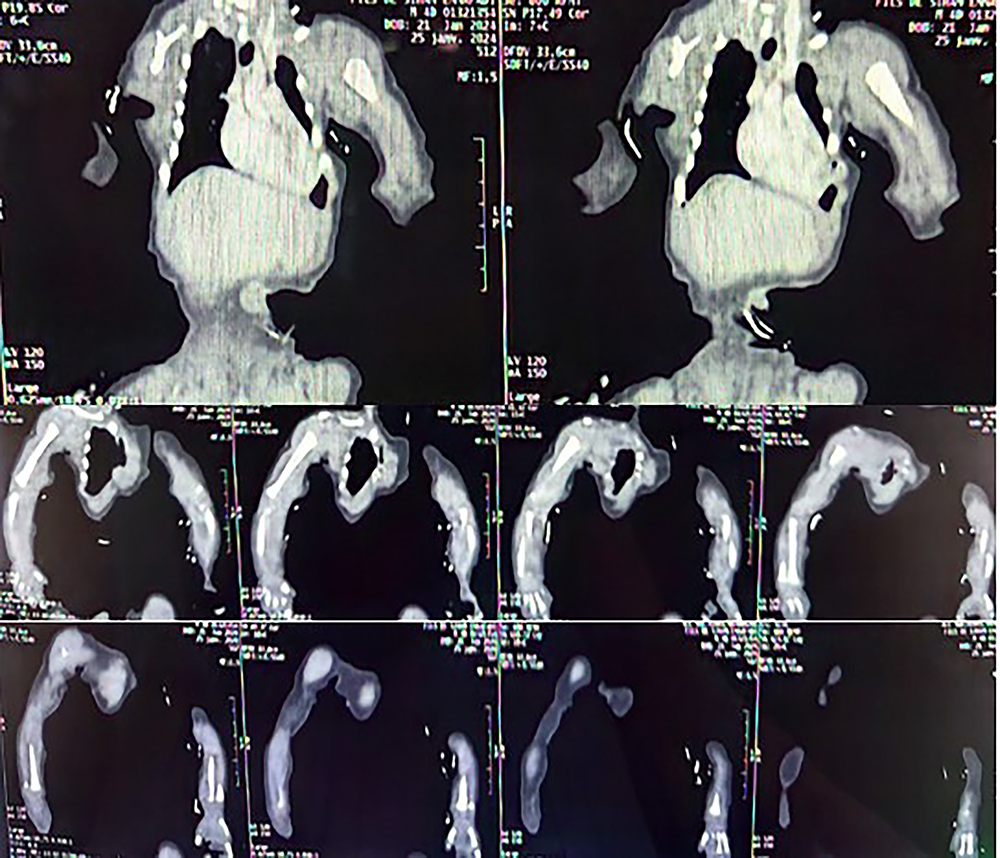

This was supplemented by an angiography scan of the upper limbs, which showed occlusion of the right humeral artery at its distal third, extending to the radial and ulnar arteries, with occlusion of the distal third of the left radial artery (Figure 2). A crash and thrombophilia assessment was requested, showing: Hemoglobin at 16.8 g/dl, platelet count at 197,000 u/l, prothrombin time (PT) normal at 100%, quick time (QT) at 11.4 sec, patient TCA/control TCA at 1.64, normal fibrinogen level at 2.4g/l, D-dimers at 2.4ug/l, hyperhomocysteinemia at 25.74 µmol/l, total protein S at 95%, normal protein C, and Factor II activity at 88.6%, FVII at 133.7%, FVIII at 200%, FIX at 101.3%, FX at 152.1%, FXI at 163.6%.

Figure 2. CT angiography images of the upper limbs showing occlusion of the right brachial artery and occlusion of the distal third of the left radial artery